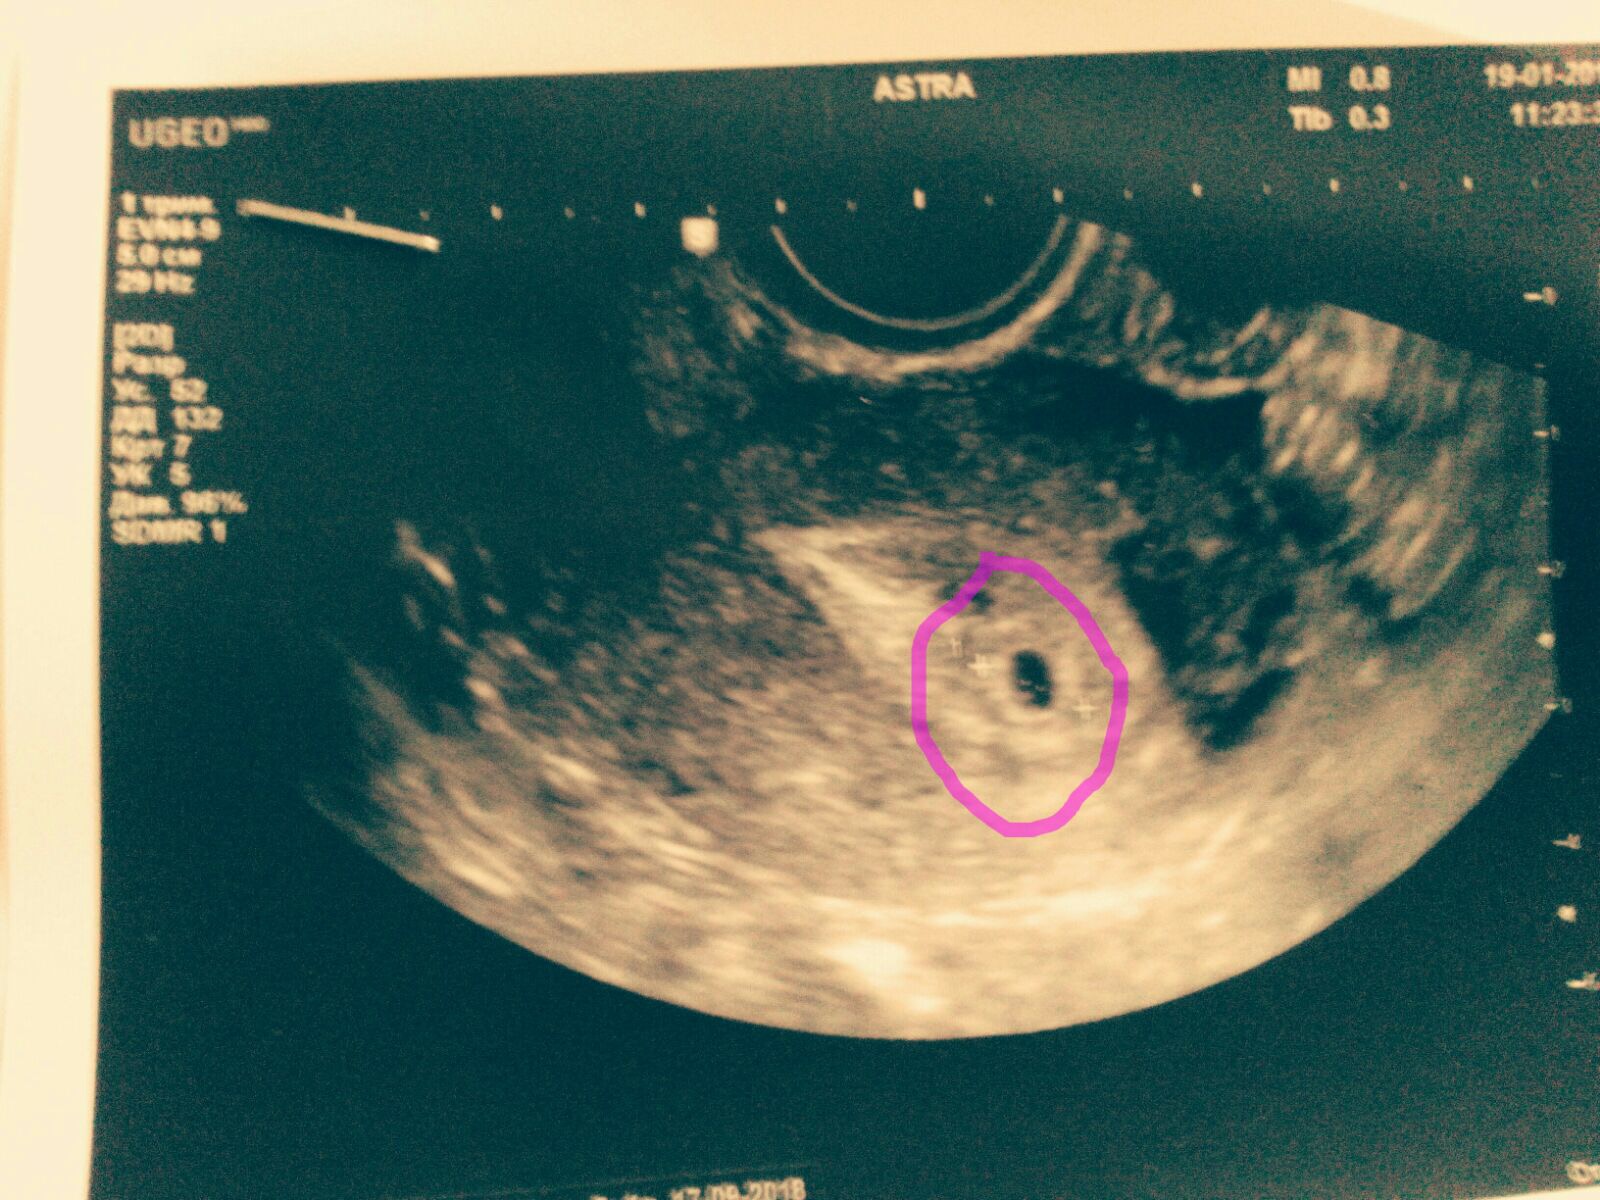

@PolishFucker, tutto questo papiro per nulla. Vorrei tanto che tu avessi ragione e che fosse una bufala, purtroppo per me non e' cosi'. Al massimo lei mi sta mettendo alla prova ma perche' utilizzare una finta gravidanza? Sarebbe gravissimo e chiuderei i ponti per primo. Poi se il concepimento e' stato fatto a novembre o dicembre, cosa cambia? @mondokane o qualcun'altro hanno tirato fuori l'opzione novembre e li ho pensato be' effettivamente ci siamo visti a novembre. Pero' chiaro novembre non regge perche' se le sue cose ritardavano me l'avrebbe detto a Natale. Sul punto 3 cosa vuoi dimostrare, cosa cambia se ci sono i visti o meno? Intendi i timbri? Sul post di Mosca puoi pensare quello che vuoi, e' un tema chiuso e sepolto. Comunque allego qui l'ecografia che tra l'altro ho girato in privato a @mondokane. Ora potete fare tutti i calcoli che volete se ne avrete voglia, io non ci capisco molto. Vedo solo la data 19 gennaio. Non si vede l'anno pero' penso proprio che sia il 2018.

La massa bianca é il sacco amniotico pieno di liquido che circonda l'ovulo concepito che diventa poi embrione e feto. Questo si trova nella cavità blu marcata di lila. Fino alla 4. settimana tutto è bianco. Nella quinta si vede la cavità blu senza niente dentro. Nell'ecografia in questione vediamo che nella cavità blu ci sono 3 "isolotti" di materia, caratteristica della 6. alla 7. settimana. All' ottava settimana i 3 "isolotti" si sono fusi in una massa compatta più grande. Dall'inizio fino all'ottava settimana un aumento da 2 mm a più di un centimetro. Si tratta quindi de entità piccolissime ma già umane. Il cuore batte dalla sesta settimana. Un cuoricino minusculo, microscopico.

Rivedendo la data dell'ecografia nell'angolo in alto a destra, si vede il giorno, il mese e l'ora, però l'anno è stato mutilato. Caso mai è un ecografia tratta dall'internet e "preparata" dalla bielorussa.

Lasciate perdere @mondokane che racconta cose a vanvera.

La camera gestazionale è visibile a volte anche dalla 3 settimana, e sicuramente dalla 4 settimana è ben visibile,

Quella dell'ecografia messa online da Viaggiatore è una camera gestazionale minuscola (va tenuto presente che è un'ecografia transvaginale, e il campo visivo totale dell'immagine è un'area molto piccola di utero) quindi va benissimo per essere della 3/4 settimana.

Tenete presente che la camera gestazionale cresce di 1 mm al giorno, quindi la frase di mondokane "è evidentissimo che si tratta della sesta alla settima settimana di gravidanza a partire la data d'inseminazione" è una cacata pazzesca..

Inoltre è sbagliata la sottofrase "settimana di gravidanza a partire (dal)la data d'inseminazione". Le settimane di gravidanza si contano a partire dall'ultima mestruazione. Quindi l'inseminazione è avvenuta 10-14 giorni dopo (e la fecondazione 14 giorni dopo).

Se indichi la luna i fessi guardano il dito... Si possono dire tante cose su questa storia, tranne che non sia possibile avere la certezza di gravidanza con un'ecografia alla 3 settimana. Inoltre l'ecografo oltre alla presenza della camera gestazionale (che c'è) riconosce anche l'aumento di dimensione dell'utero e l'inspessimento dell'endometrio.

Con la mia analisi dell'ecografia del Viaggiatore Nero sono sulla retta via, si tratta della sesta o settima settimana a partire dalla fine del ciclo che come dice l'Europeo è di circa due settimane

prima dell'inseminazione del 25.12.2017. La fine del ciclo sarebbe dunque verso il 10.12.2017.

Tra lì e il 19.01.2018 ci sono 40 giorni, dunque da 6 a 7 settimana.

Ciò comproverebbe che la ragazza può essere stata messa incinta nel periodo di Natale 2017 e che è una persona responsabile e coerente avendo fatto fare un'ecografia nella sesta o settima settimana.in caso di una gravidanza.